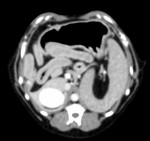

CT検査にて肝臓の器質的変化や門脈体循環シャント(※)がないか確認したのち、肝生検を実施した。

CTでは腫瘤病変など画像診断で検出できる器質的な変化は認められず、シャント血管も認められなかった。